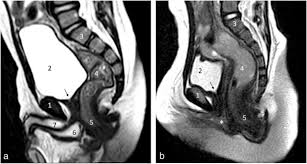

33+ Mri Pelvis Anatomy Female. Mri can not have harmful effects on the body. The superior tissue contrast and flexible imaging planes afforded by magnetic resonance imaging (mri) versus competing technologies permit optimal depiction at the authors' institution, the female pelvis protocol is performed for suspected ovarian, uterine, vaginal, or bladder pathology;

Magnetic resonance imaging or mri of the female pelvis offers a unique display of the pelvic anatomy, including a woman's ovaries, uterus, and fallopian tubes. Start studying normal female pelvis anatomy. With its help, it is realistic to study the female pelvis and get comprehensive information about the state of all organs of the human body.